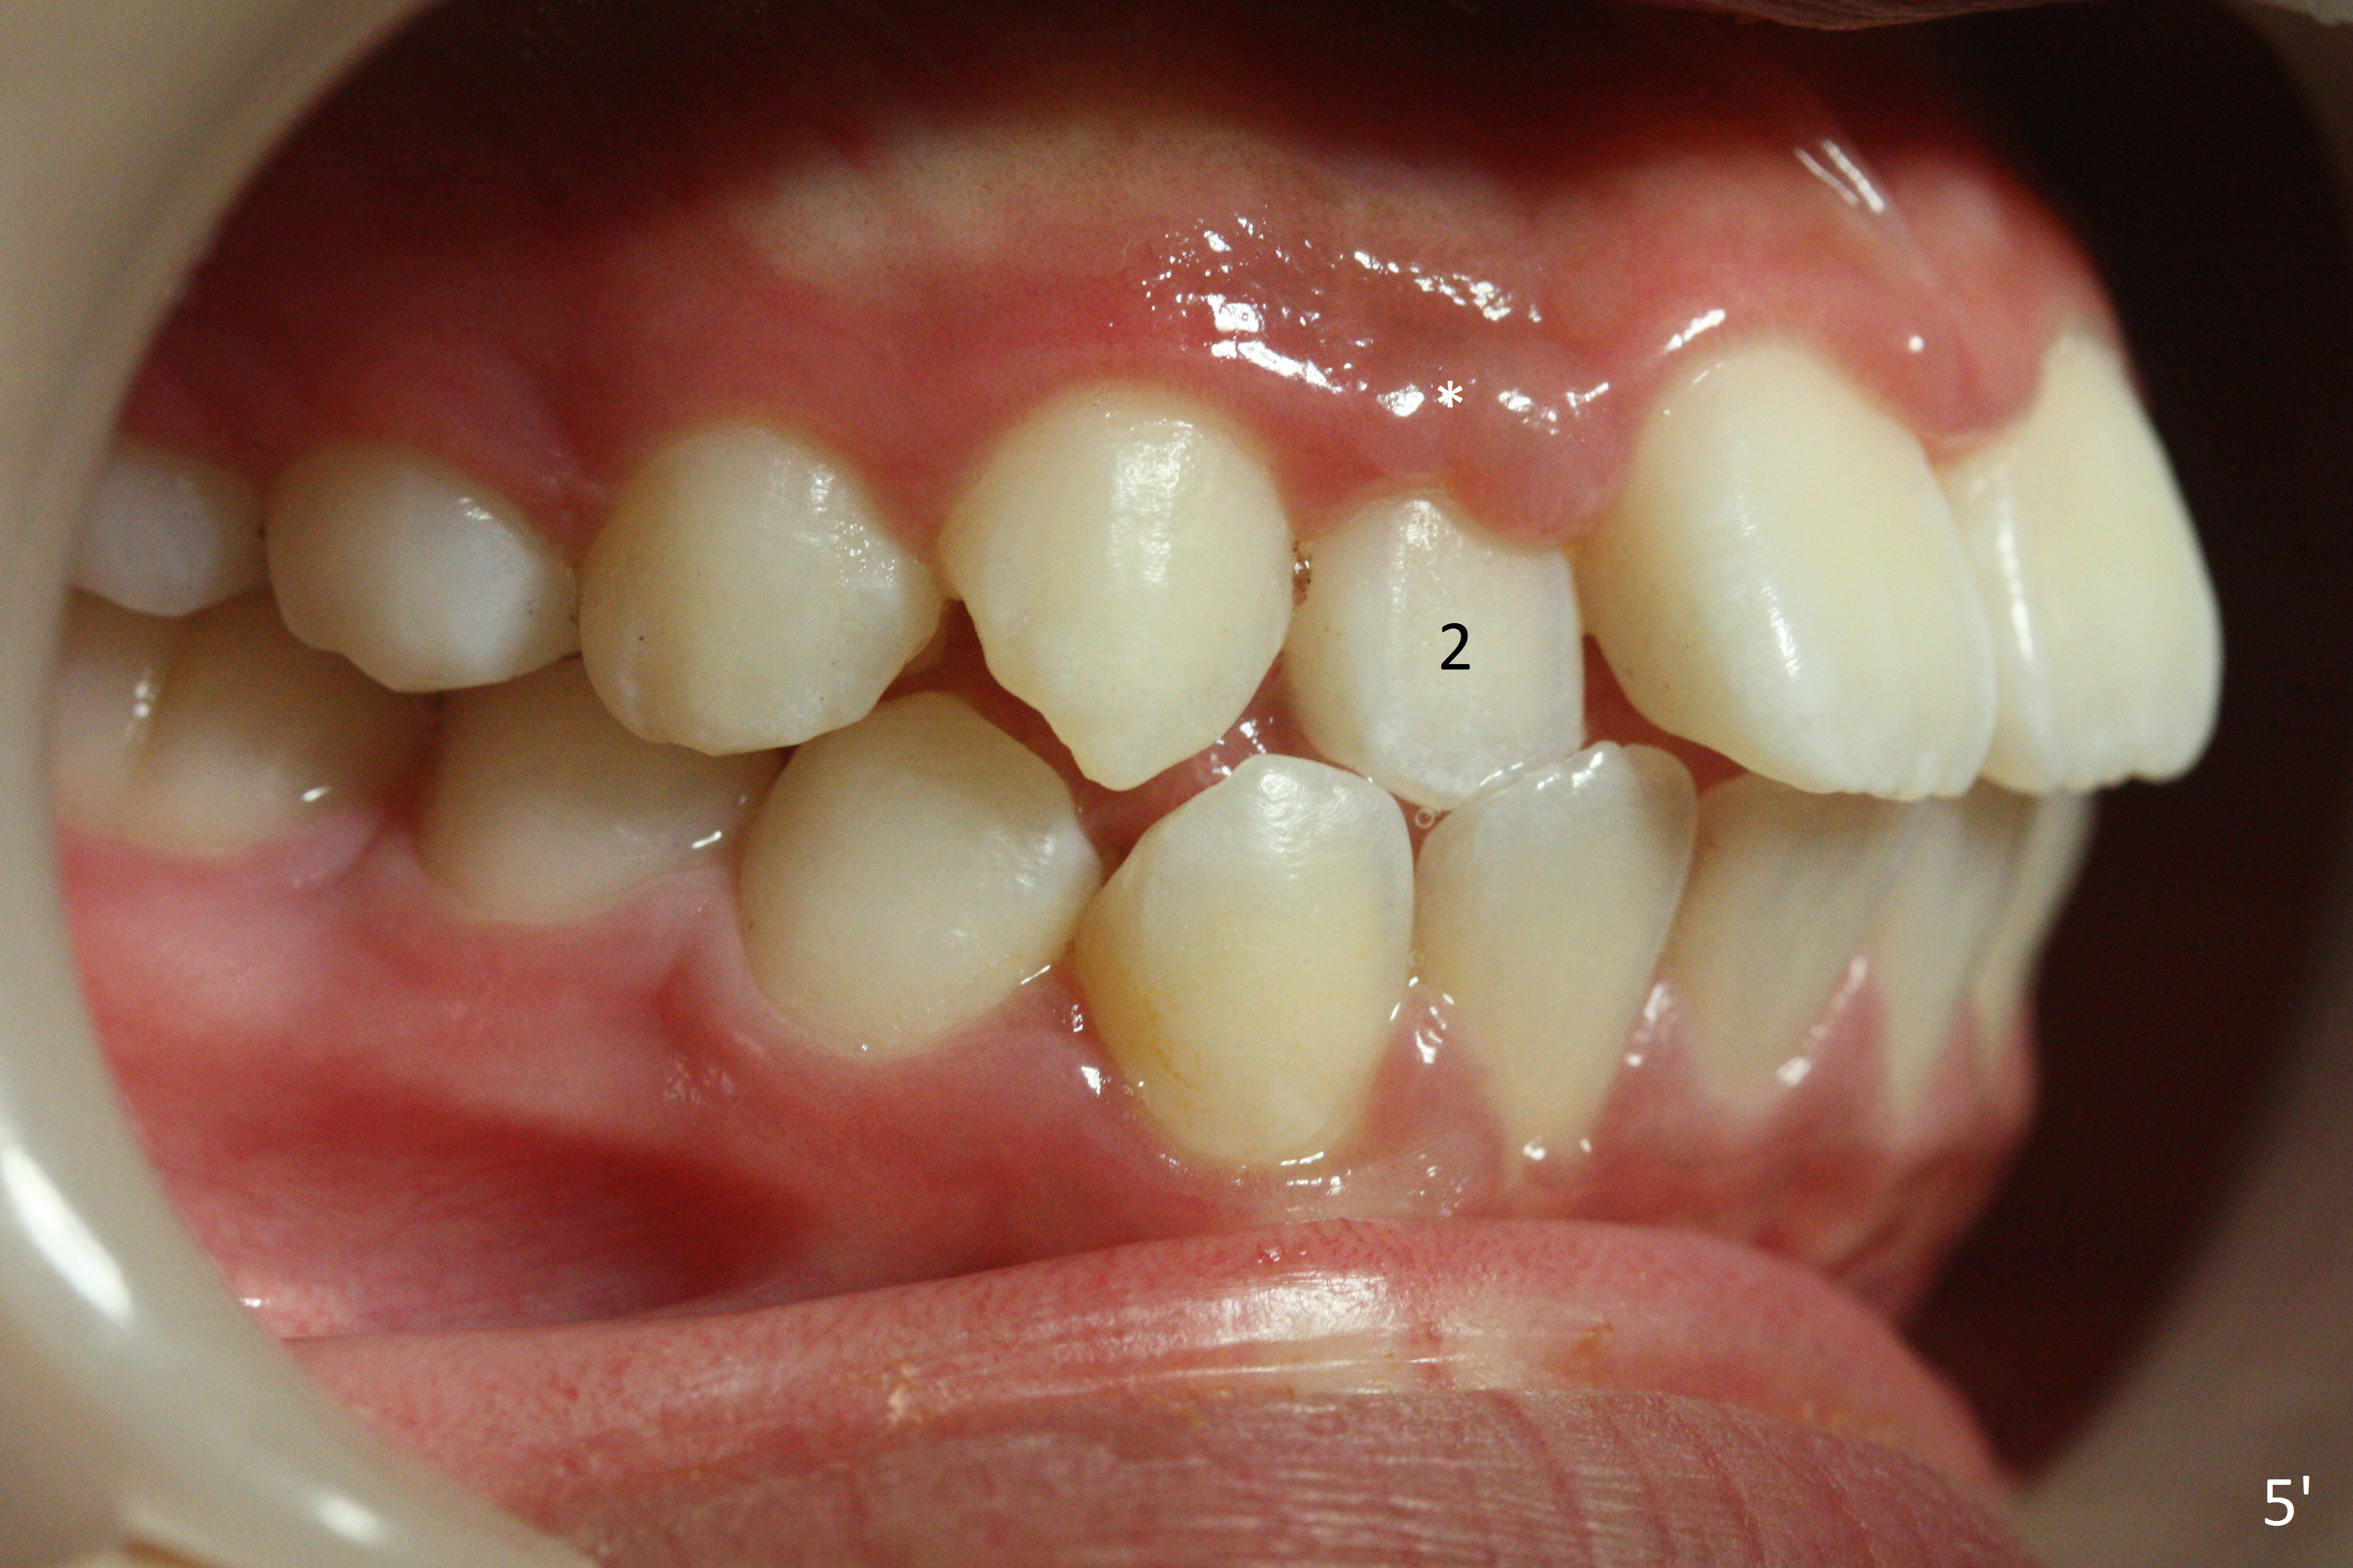

Two sisters (Sophia, 13 years old and Selina, 11) present to clinic for orthodontic treatment. Dental anomalies of Sophia include microdontia of the upper lateral incisors and congenital missing of the upper right permanent canine (Fig.5,6). For Selina, the upper right lateral incisor (Fig.5') and the upper left second bicuspid (Fig,6') are in cross bite.